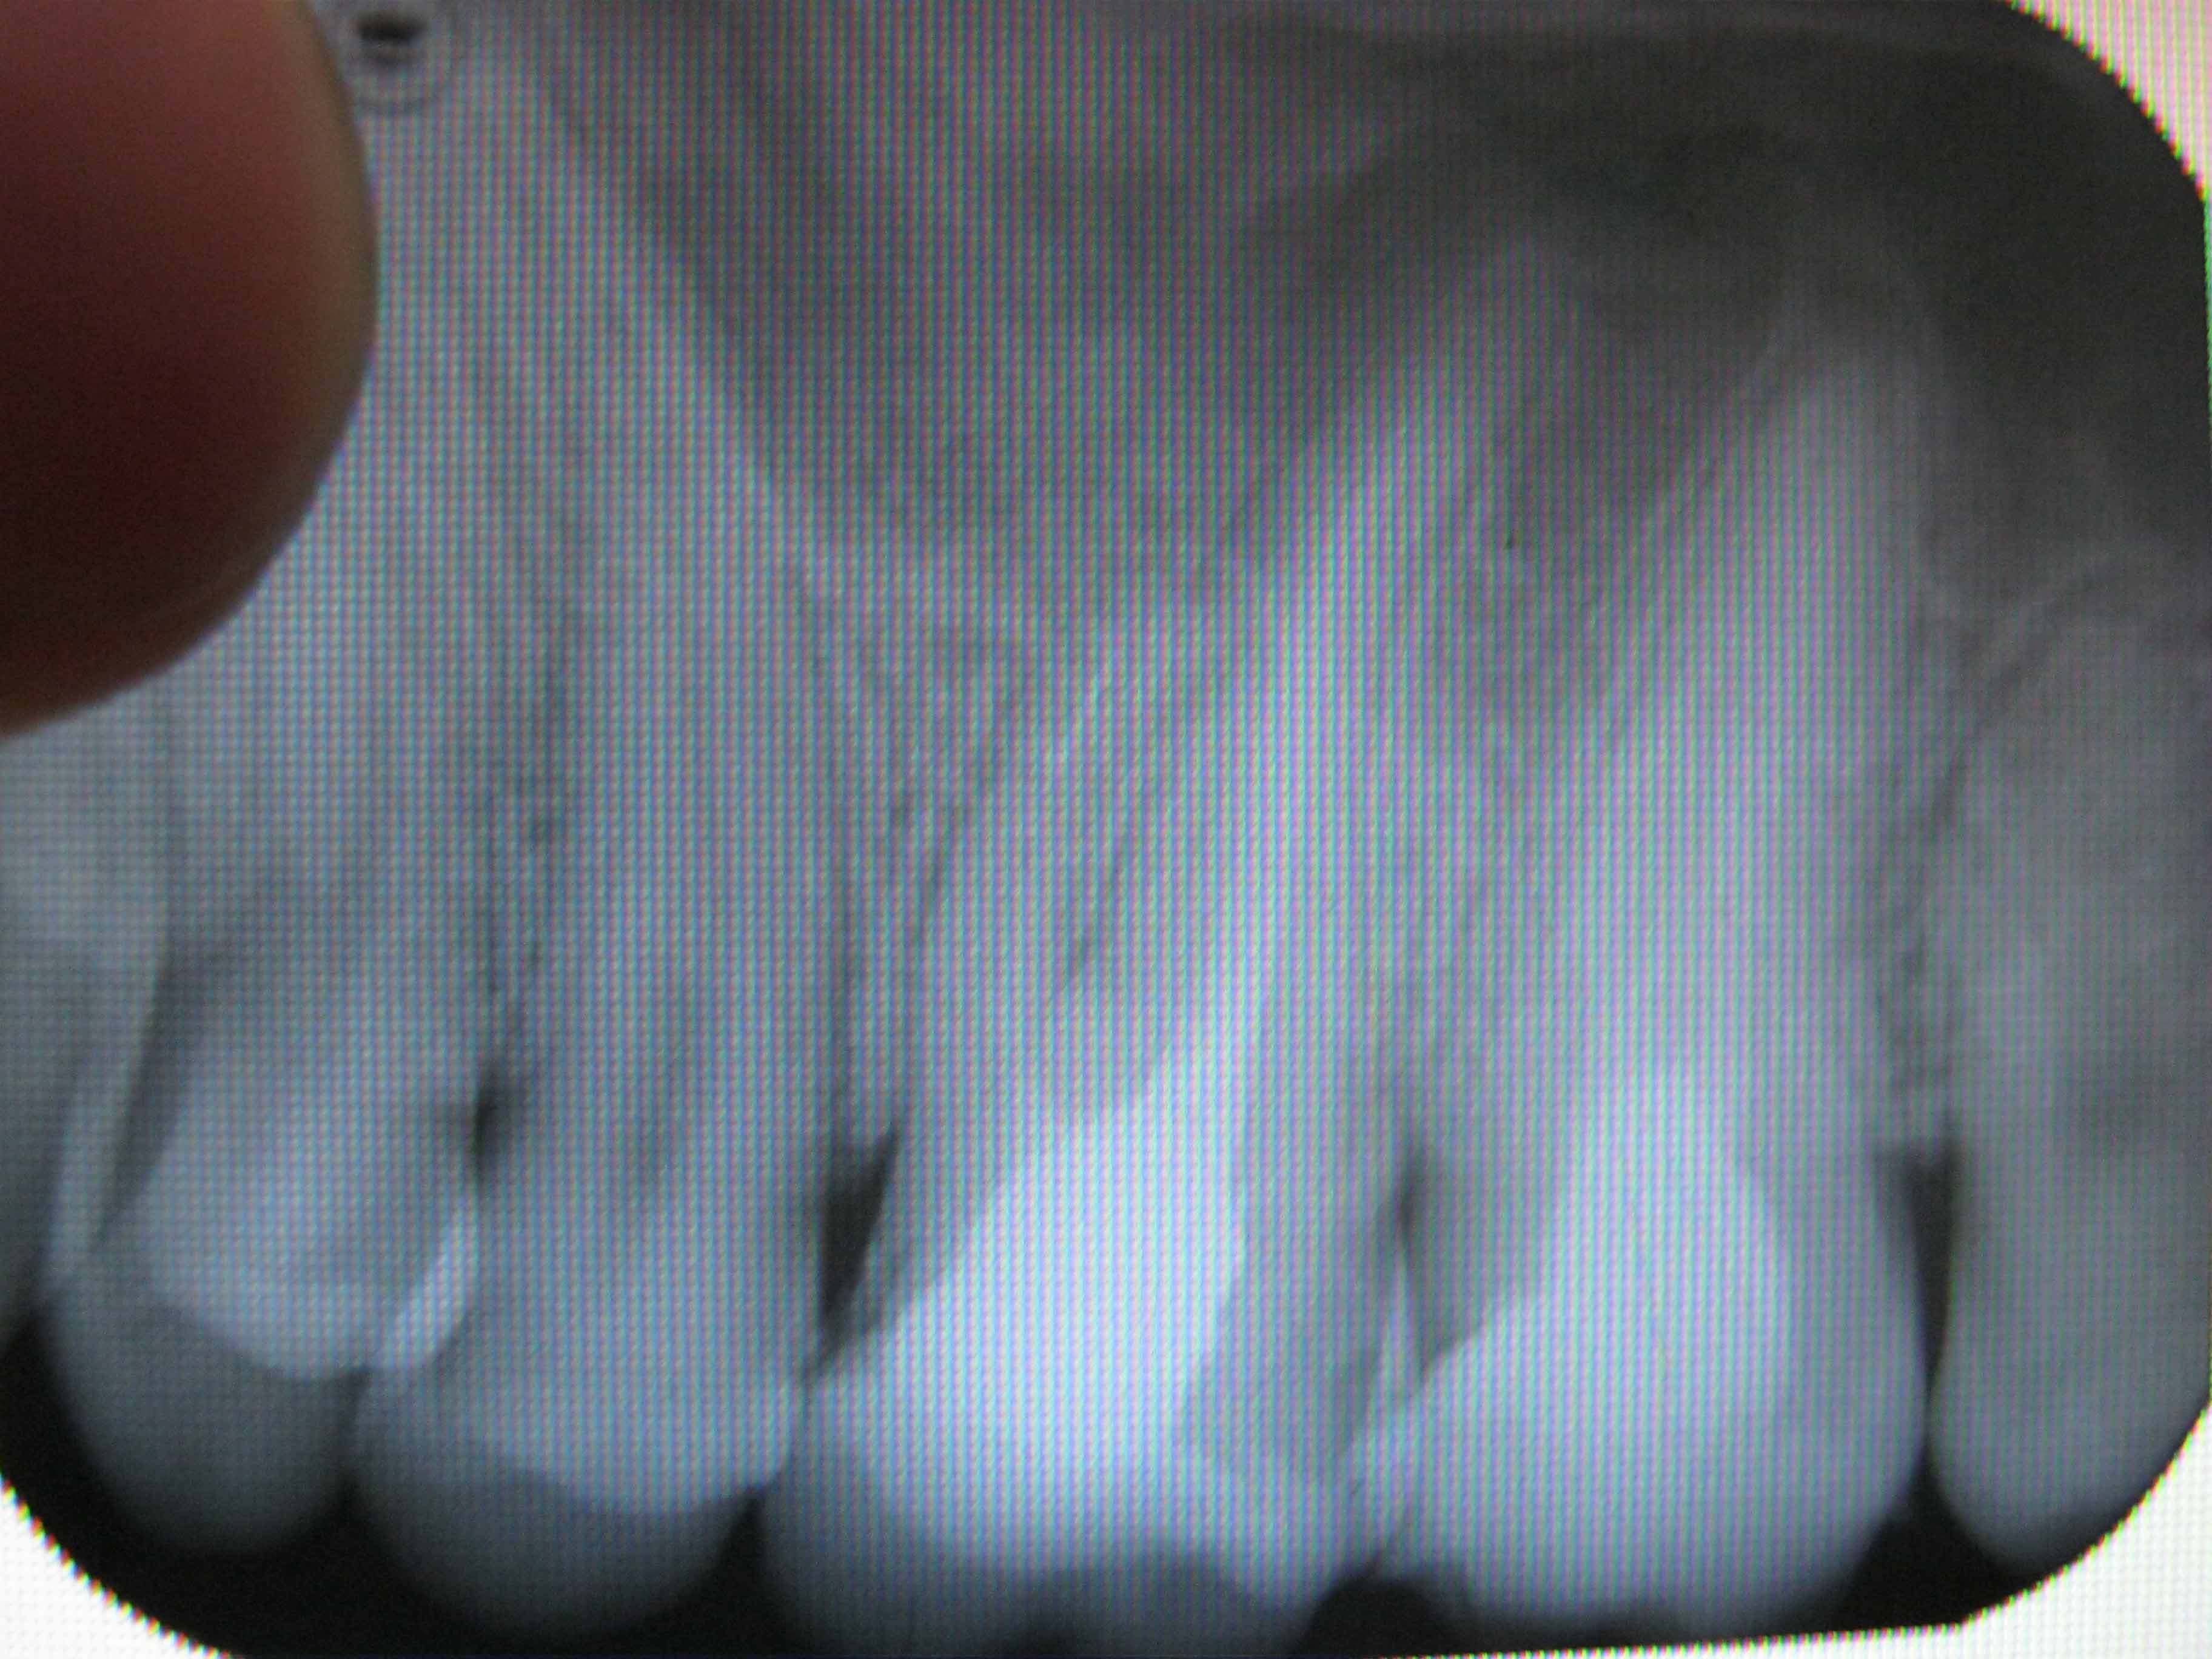

вот снимки.

сегодня зашол ещо к одному врачу он сказал что можно поставить коронку а если когда-нибуть заболит то прооперировать и вырезать это образование. А какие варианты лечения есть, кроме оперативных и есть ли они?? Спасибо.

Нда.... Такой отломок достать будет очень и очень сложно.

Нужно попробовать если уж не извлечь, то хотя бы обойти его. Если извлечь или обойти этот отломок не получится, то все остальные варианты не очень хороши в плане прогноза.

Да, отломок иглы. Образование - ерунда. Если канал удастся нормально вычистить, то это образовапние через несколько месяцев закроется.